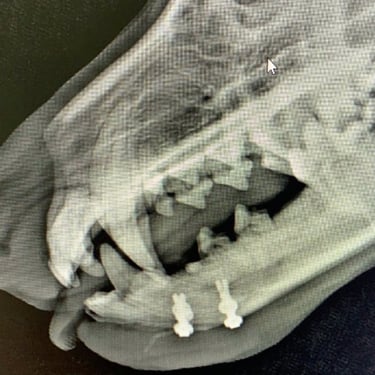

Clavos intramedulares: se colocan dentro del canal medular y proporcionan soporte principalmente contra fuerzas de flexión. Suelen utilizarse en fracturas diafisarias y, en muchos casos, se combinan con cerclajes o fijadores externos para mejorar la estabilidad rotacional.

Cerclajes y alambres: se emplean como método de soporte adicional, principalmente en fracturas en espiral o con fragmentos largos, ayudando a mantener la reducción y la compresión de los fragmentos.